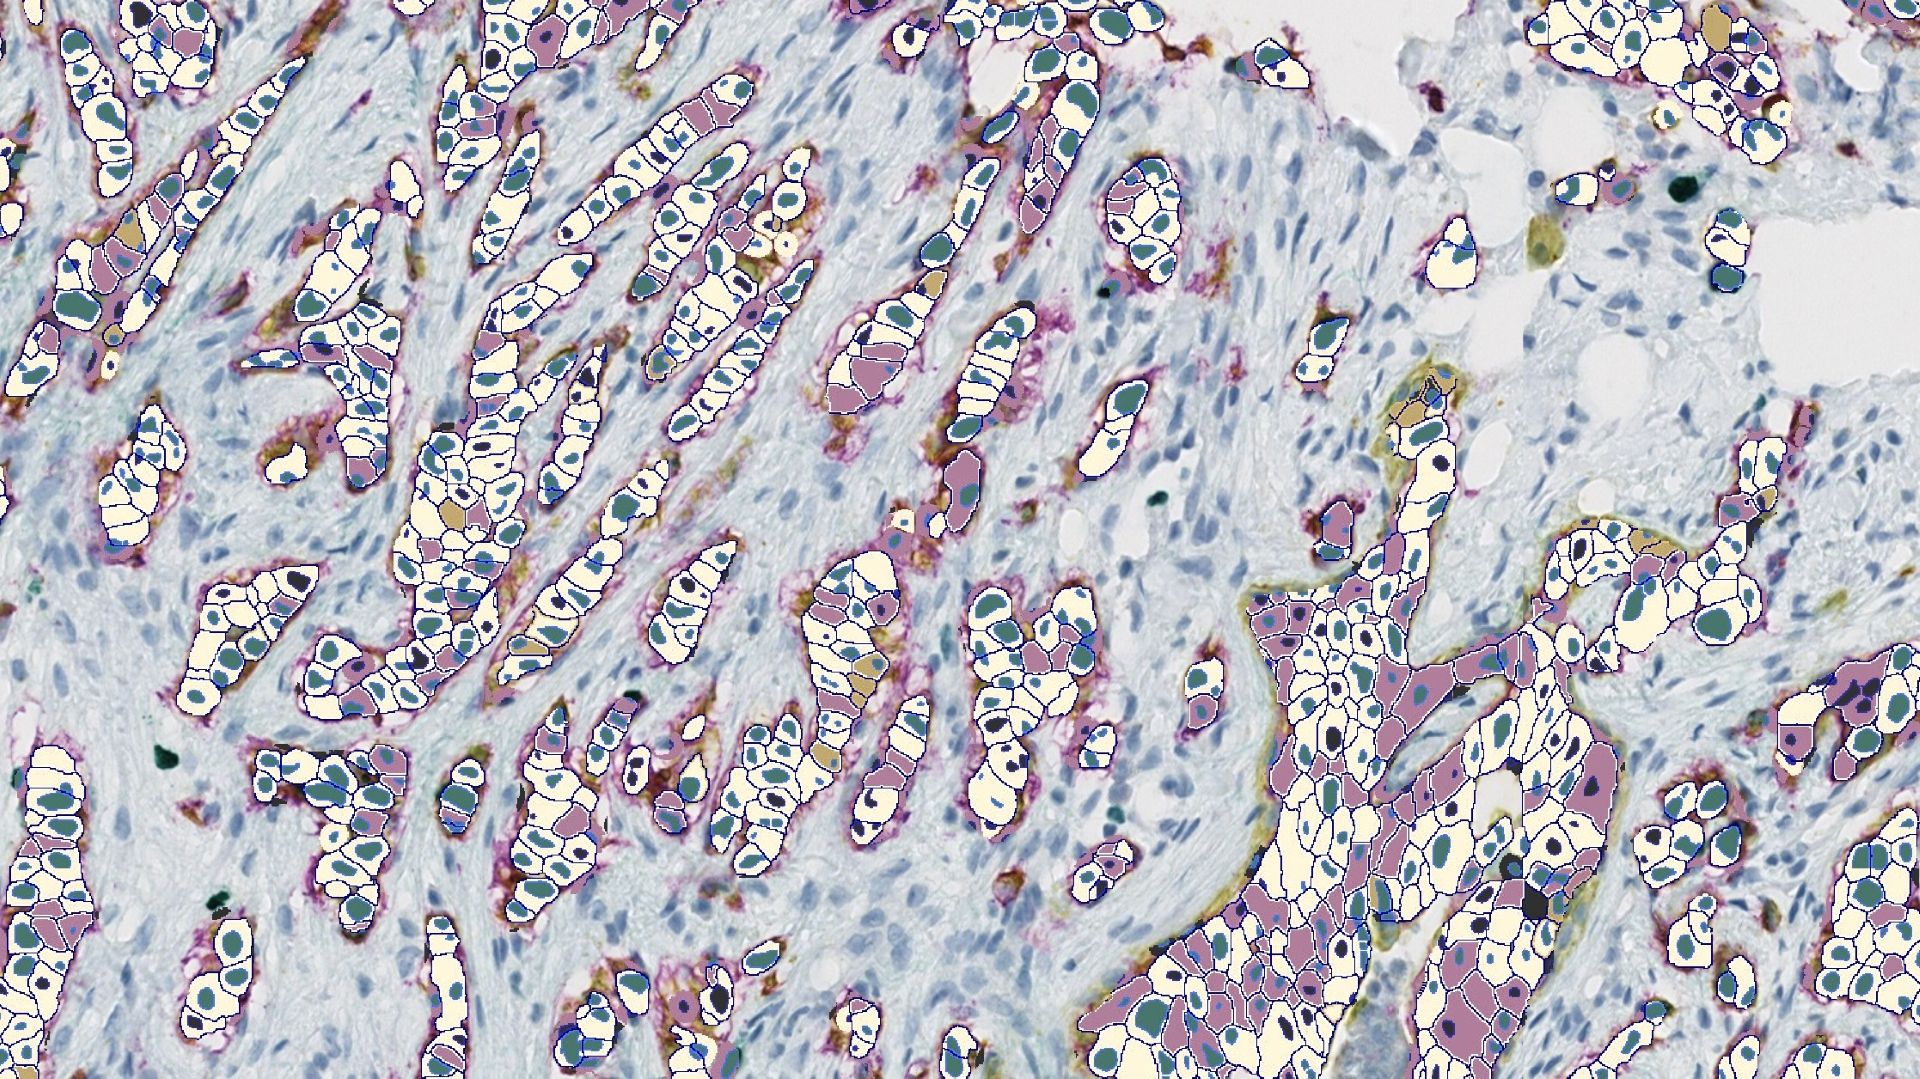

HALO image analysis provides researchers with per-cell, compartment-level expression data, including both intensity values and positivity classifications, if defined, and can include AI tissue classifiers to focus analysis on the tissue class(es) of interest.

• Tissue classification: Tumor and stroma or other classes of interest are delineated using deep-learning networks developed using HALO AI.

• Nuclear and membrane segmentation: Additional HALO AI networks power nuclear and membrane segmentation, enabling accurate definition of ADC-positive and ADC-negative cell populations and analysis of biomarker distribution in cells.

• Biomarker quantification: Target expression is assessed by QCS, in which biomarker expression is quantified as mean optical density in the segmented cell nuclei, cytoplasm, and membrane. QCS enables spatial analysis of biomarker location in cells, with distribution of some targets, such as TROP2, having been shown to be predictive of clinical outcomes.⁵ HALO has offered per-cell, compartment-level intensity data for over a decade, and the Pharma Services team has extensive experience leveraging this objective and continuous data.